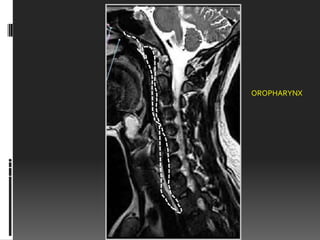

OROPHARYNX